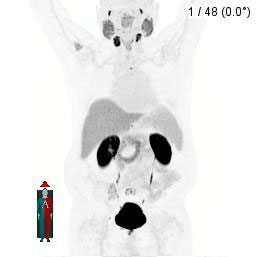

A repeat PET/CT (figure 2) showed considerable interval improvement in skeletal metastatic lesions, including the site of lower back pain.

Taking advantage of unique quantitative assessment of PET/CT we performed tumor burden assessment before and after 177Lu-PSMA-617 treatment cycles (figure 3), which showed 85% decrease in his total body tumor burden after 4 cycles of Lu-177 PSMA therapy.

PSA levels went down from 1.15 ng/mL before initiation of 177Lu-PSMA-617 to 0.48 after four cycles of therapy. Since the most recent PSMA PET/CT still shows small volume of residual PSMA-avid skeletal metastatic lesions our plan is to continue remaining 2 cycles of therapy.